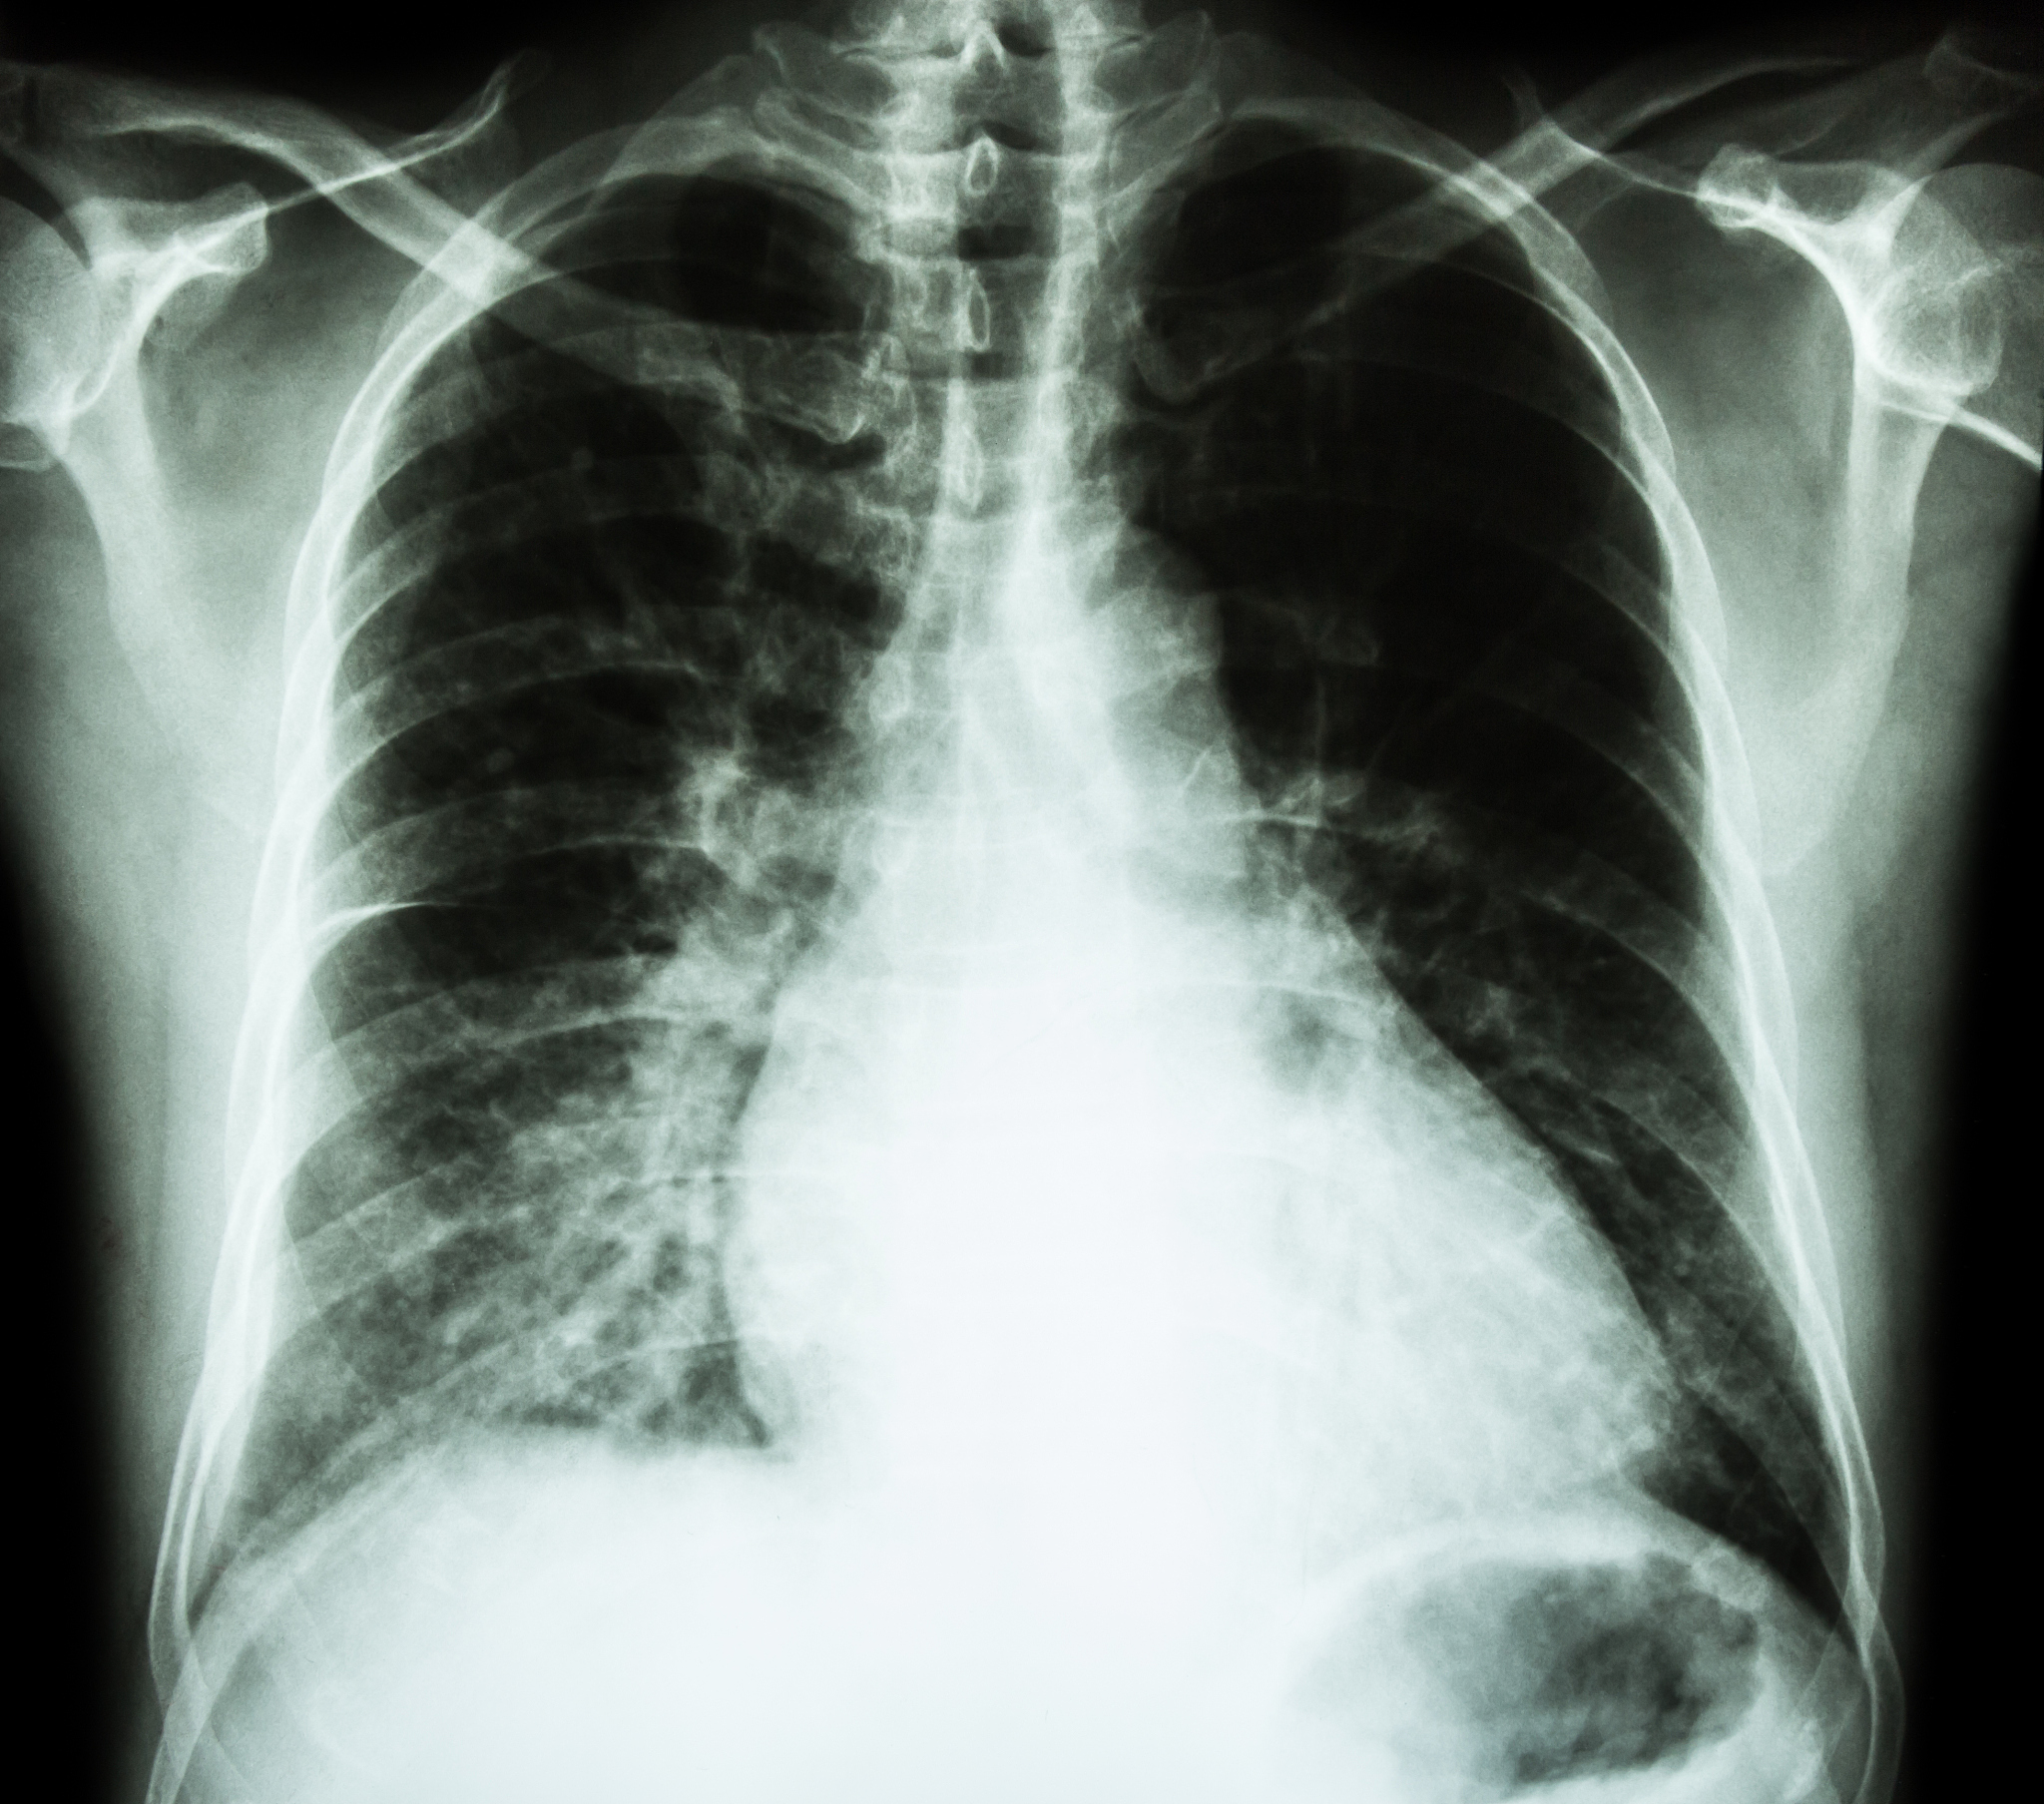

心衰的指标通常是通过测量心房利钠肽前体(NT-proBNP)的水平来确定的。NT-proBNP是一种由心脏产生的激素,其水平可以反映心脏扩张和心肌受损的程度。正常情况下,NT-proBNP的水平较低,通常在0-125 pg/mL范围内。然而,心衰患者的NT-proBNP水平通常会升高,且高于1000 pg/mL,以提示心衰的可能性。需要注意的是,心衰的确诊不能仅仅依靠NT-proBNP水平,还需要综合考虑患者的症状、体征和其他相关检查结果。因此,如果您怀疑自己或他人可能患有心衰,请务必咨询医生进行确诊和治疗。

心衰的指标为1000pgml